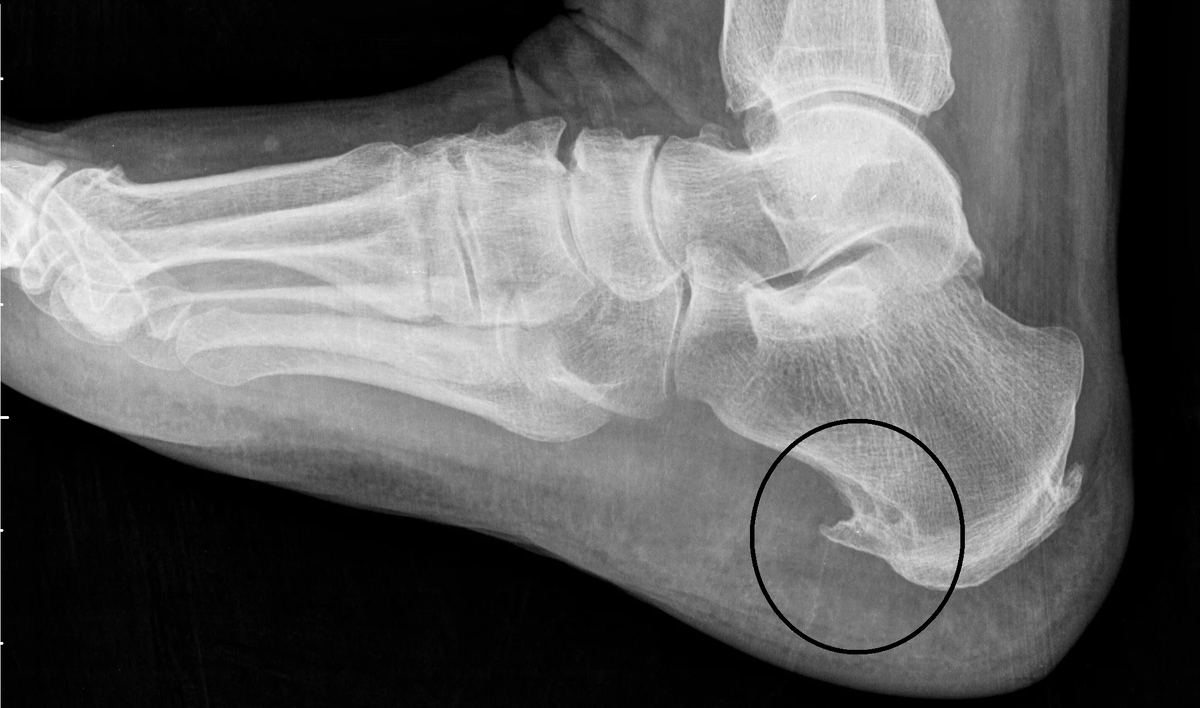

Пяточная шпора — это одна из наиболее распространённых причин боли в пятке, которая может серьёзно повлиять на качество жизни. Появление пяточной шпоры связано с образованием кальциевого нароста на подошвенной части пятки, где прикрепляется подошвенная фасция — соединительная ткань, которая поддерживает свод стопы.